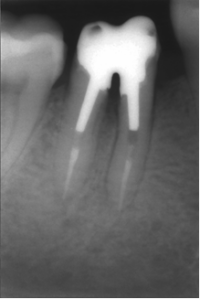

Perforation du placher pulpaire et faux canal.

Perforation du plancher pulpaire et faux canal.